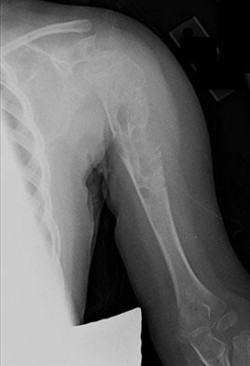

A 15-year-old male presents with deep knee pain awakening him at night. Radiographs show a permeative destructive lesion in the distal femoral metaphysis with a 'sunburst' periosteal reaction and Codman's triangle.

Biopsy confirms high-grade conventional osteosarcoma. What is the most critical prognostic factor for long-term overall survival in this patient?

Explanation

For localized high-grade osteosarcoma, the most important prognostic indicator is the histologic response to neoadjuvant chemotherapy. This is evaluated during the definitive resection. A 'good response' is typically defined as greater than 90% or 99% tumor necrosis. Patients who achieve this level of necrosis have a significantly improved disease-free and overall survival rate compared to 'poor responders' who have extensive viable tumor cells remaining.